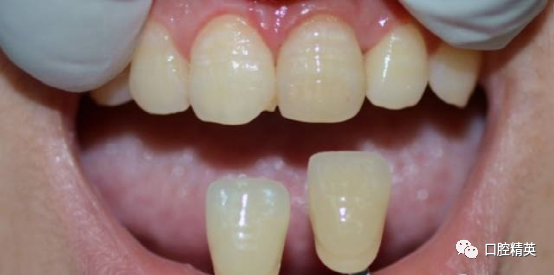

患者,女,31岁。于我院行21根管治疗。21呈生理动度。与邻牙参照略有变色。治疗数周无急性症状,但偶有不适。21唇侧根尖区有膨隆感,扪诊(+),质软,局部牙龈略红肿。转诊时口内照

术前口内照